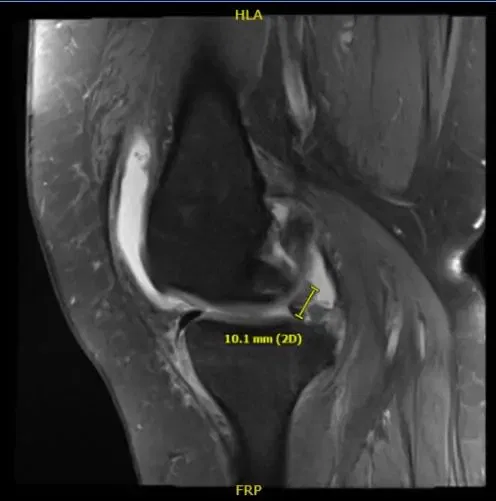

Resonancia magnética de la rodilla derecha

Impresión del resultado de la resonancia magnética es la siguiente: edema de médula ósea en la parte periférica anterior de la meseta tibial medial con ligera aplanamiento e irregularidad de la superficie articular; hay una impactación subcondral de bajo grado o fractura por estrés en cicatrización.

Desgarro complejo del cuerno posterior del menisco medial, incluyendo un colgajo meniscal desplazado que adentra en la raíz posterior y mide 1 cm de longitud. Artrosis patelofemoral severa. Artrosis femorotibial moderada. Derrame articular moderado.